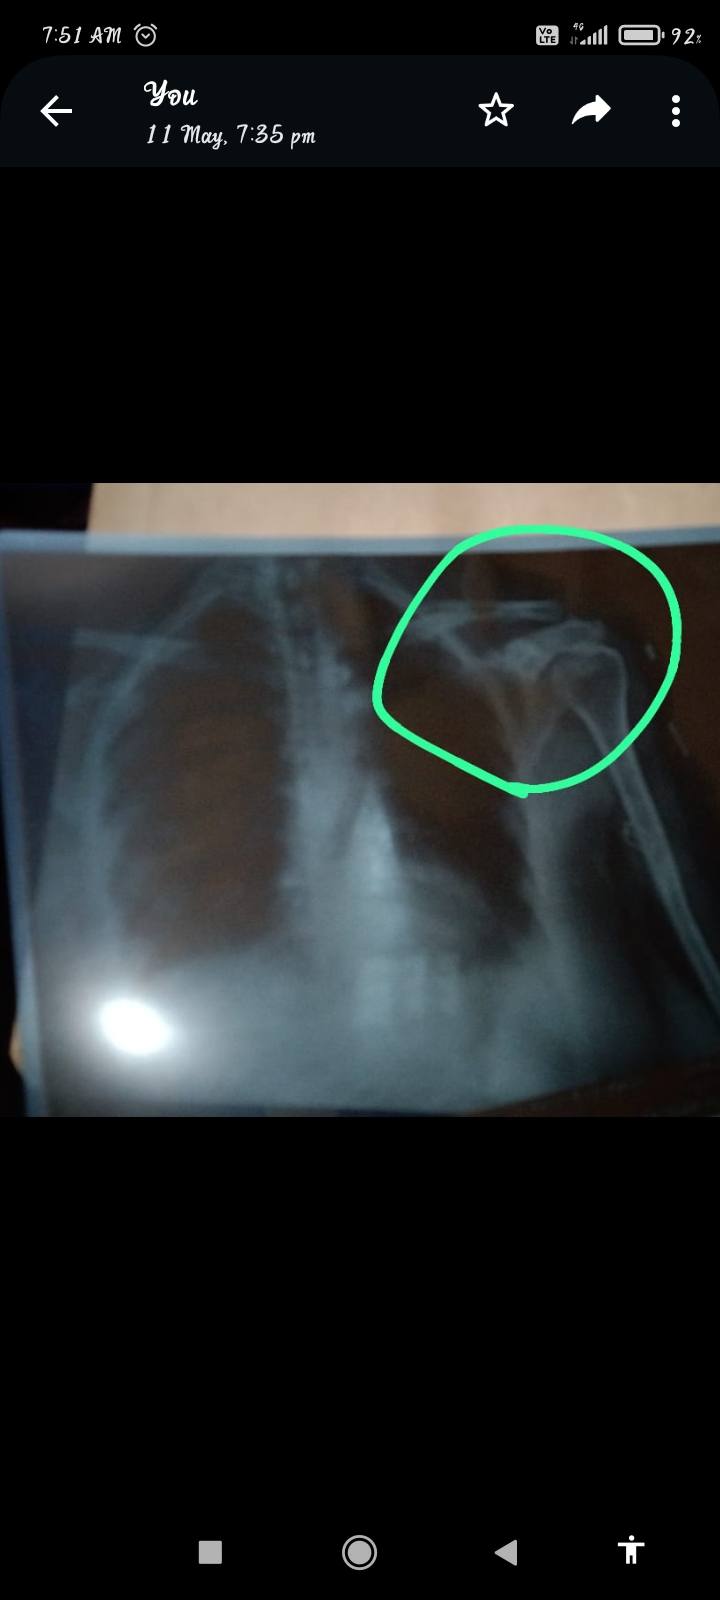

Sir mere mother ka exsident mai shoulder mai fracture aa gyia aap dekh kar mujhe dekh kr btate ki yeh kaise thik hoga